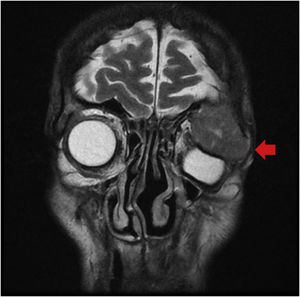

Paciente varón de 83 años sin antecedentes de interés que consulta por proptosis y diplopía en el ojo izquierdo de reciente comienzo. Se realiza tomografía craneal (fig. 1) y resonancia magnética (fig. 2) donde se objetiva masa heterogénea en la glándula lacrimal izquierda con invasión ósea del reborde orbitario supero-lateral. Se biopsia la lesión lacrimal descrita, evidenciándose datos compatibles con lesión metastásica de origen intestinal. Dados los hallazgos se realiza estudio de extensión, evidenciándose adenocarcinoma de recto superior avanzado (T3N2bM1c), asociado a metástasis hepáticas y óseas. Debido a lo avanzado de la enfermedad fue tratado con radioterapia paliativa orbitaria y quimioterapia paliativa.